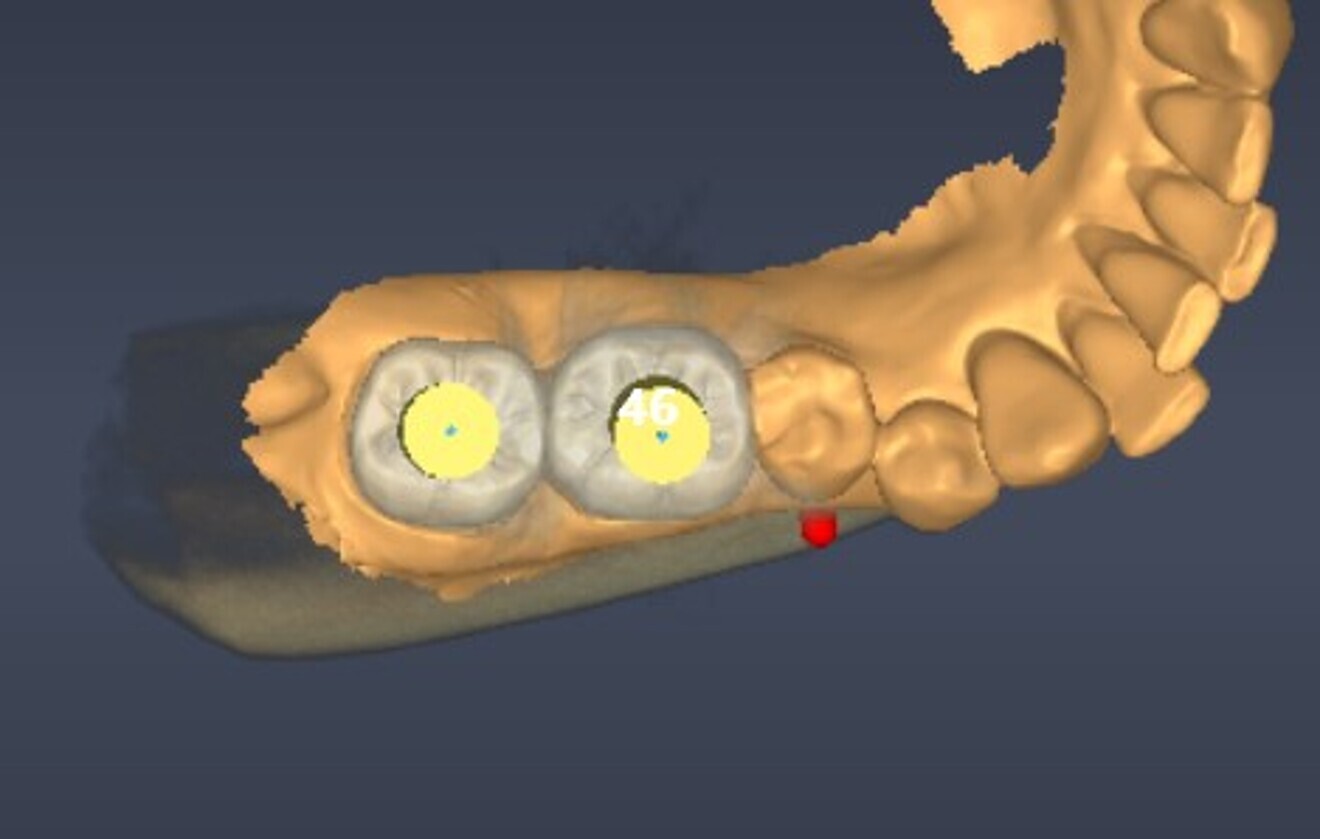

A guided surgical approach was selected, specifically a sleeveless guide, to make use of the precision that it affords in such cases. The DentiqGuide software (3DII) was used to plan treatment in order to establish precise implant positioning. The surgical guide was then printed on a Sonic Mini 8K S (Phrozen), ensuring high accuracy in execution.

Fig. 4: Digital implant planning, occlusal view.

Fig. 5: Digital implant planning, labial view.